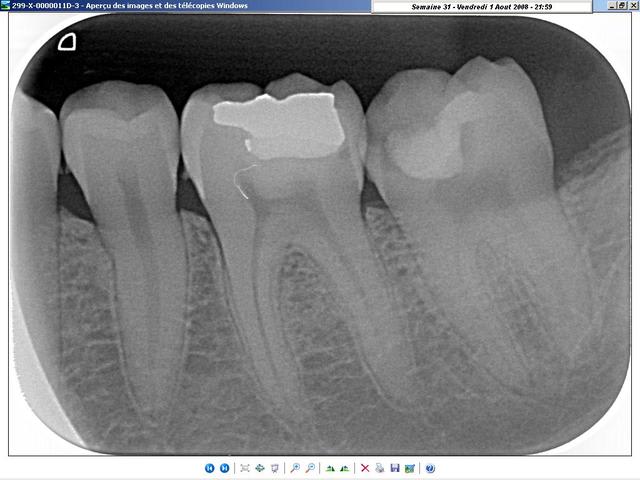

radiologiquement, je ne vois pas trop de différences. A vous de juger.

Les deux cas sont de cette semaine, celui du condenseur, tout frais de cet après-midi; La gutta doit encore être tiède... lol ;-)

sur ce coup, j'étais bien content d'avoir le thermafill (en prêt)!

j'ai préféré faire l'endo plutôt que de galérer à la virer... ^^

il ne te reste plus qu'a faire aussi bien sur la 36!